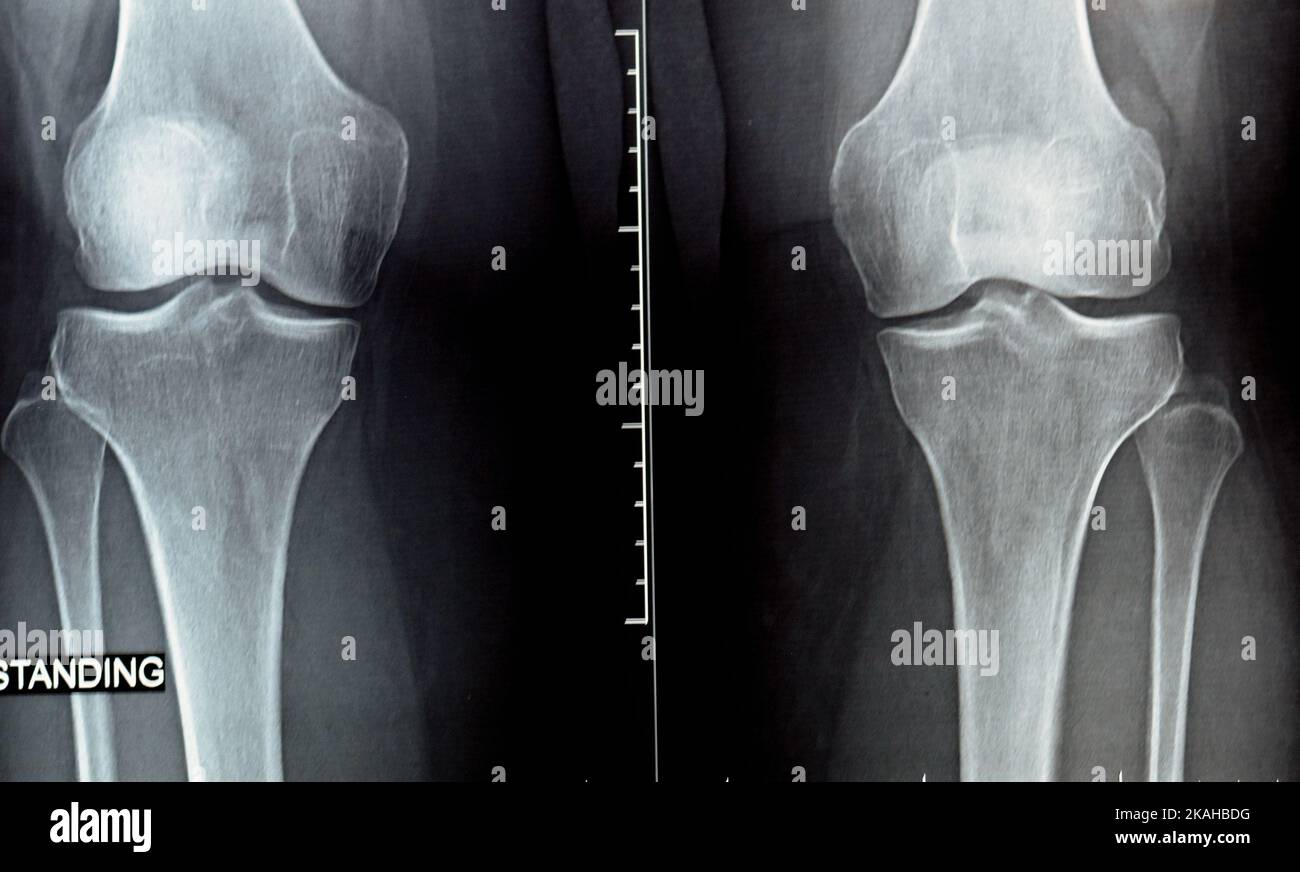

(A) Radiographs of the knee showing loss of joint space and subchondral What Is Articular Sclerosis Subchondral bone sclerosis, together with progressive cartilage degradation, is widely considered as a hallmark of oa. Despite the increase in bone volume. Subchondral sclerosis occurs because of increased bone density or thickening in the subchondral layer. It shows up in the later stages of osteoarthritis. Everything you should know about joint space narrowing. If you’ve been diagnosed with. Osteoarthritis can. What Is Articular Sclerosis.

Radiografía simple en la articulación de la rodilla que muestra What Is Articular Sclerosis Despite the increase in bone volume. Osteoarthritis can cause bone thickening. Subchondral sclerosis occurs because of increased bone density or thickening in the subchondral layer. Subchondral sclerosis is the hardening of the tip of a bone just below the cartilage. If you’ve been diagnosed with. Subchondral bone sclerosis, together with progressive cartilage degradation, is widely considered as a hallmark of. What Is Articular Sclerosis.